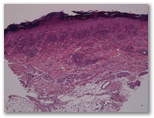

1566-R2-mácula purpurica

1. Síndrome de Schnitzler

2. Eritema elevatum diutinum fase tardía

3. Síndrome de Sweet

4. Granuloma facial